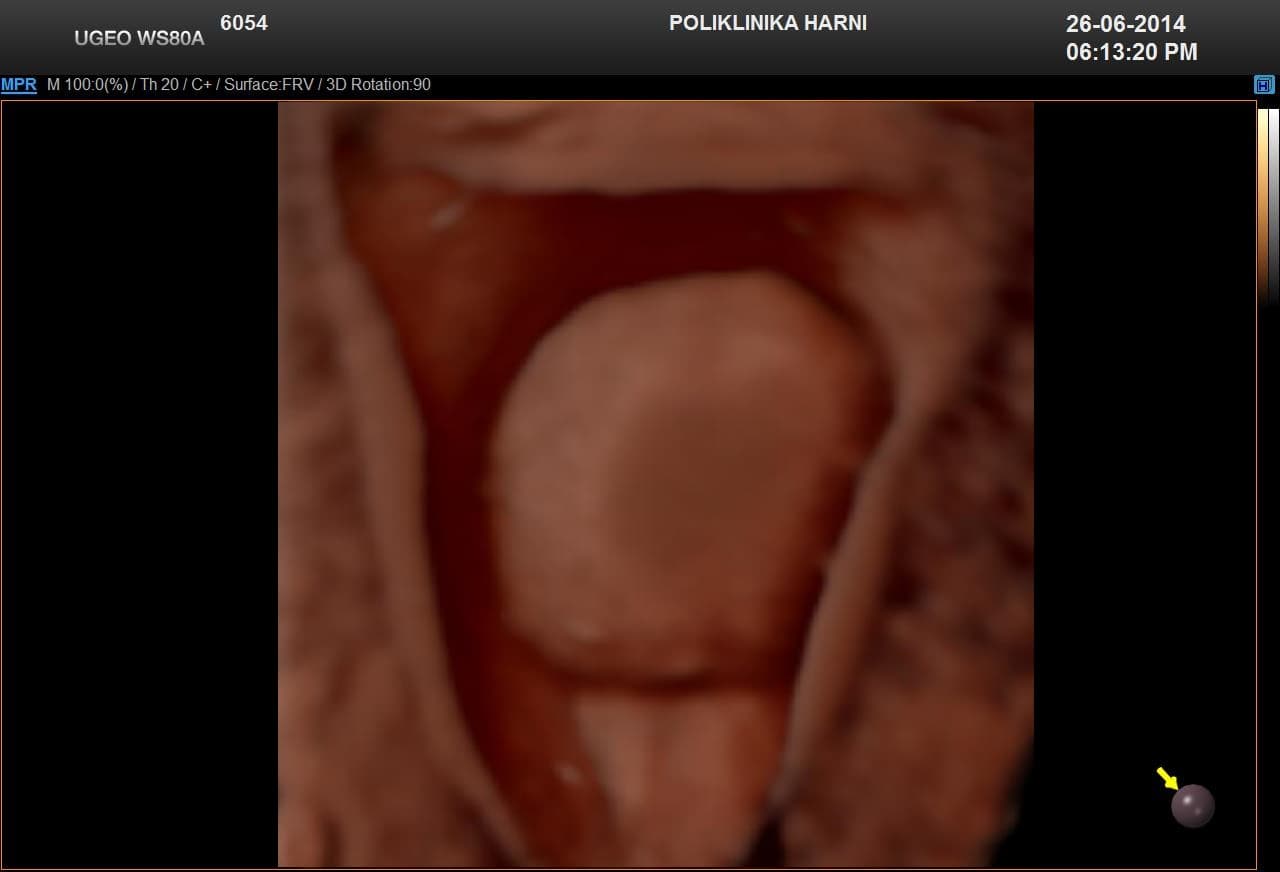

Kontrastni ultrazvukobojenim doplerom i 3D ultrazvukom / Hy-Co-Sy - hysterosalpingo-contrast-sonography sigurna je i učinkovita dijagnostička metoda u procjeni prohodnih jajovoda i od presudnog značenja u obradi neplodnih pacijentica. Provodi se u prvom dijelu menstruacijskog ciklusa nakon potpunog prestanka menstruacijskog krvarenja. Nakon pripreme pacijentice, u kanal vrata maternice se uvodi kateter i ubrizgava kontrast, a potom se prikazuju maternična šupljina, strukture unutar nje, eventualne anomalije maternice i prohodnost jajovoda. Kontraindikacije su trudnoća, krvarenje, akutna zdjelična upala i adneksalni tumor.

Pojava više-dimenzionalnog ultrazvuka omogućuje vizualizaciju ne samo određenih dijelova uterusa nedostupnih dvodimenzionalnom prikazu uslijed položaja uterusa, već i odabir optimalne ravnine kao i načina prikaza sumnjive lezije, a kod 5D ultrazvuka tehnološke inovacije omogućuju dodatne automatske presjeke koji omogućuju slojevitiju sliku i daju dubinu slici ujedno poboljšavajući dijagnostičku točnost. U dijagnostici anomalija uterusa trodimenzionalna rekonstrukcija ima prednost nad dvodimenzionalnim prikazom, te se njegova točnost može mjeriti s točnošću histerosalpingografije.

5D ultrazvučna tehnologija označuje dodatnu, vrhunsku kvalitetu revolucionarnog ultrazvučnog sustava uz automatizaciju tehnike koja više nije apsolutno ovisna o ultrasoničaru, uz najveću kvalitetu dijagnostičkog prikaza na LED monitoru i optimiziranim softverom, koji omogućuje novu slojevitu, dubinsku sliku poput CT prikaza u stvarnoj trećoj dimenziji u svim otvorenim pitanjima kako u ginekologiji, tako i opstetriciji.